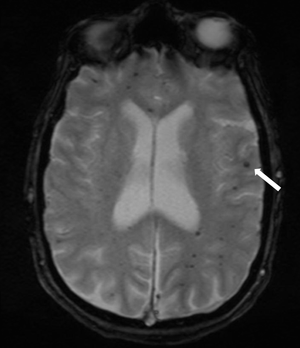

A Clinical Update of Intracerebral Hemorrhage

ByAlice Cai, MD,Xuemei Cai, MD

A summary of current treatment guidelines, application, and emerging developments in the area of spontaneous nontraumatic ICH.